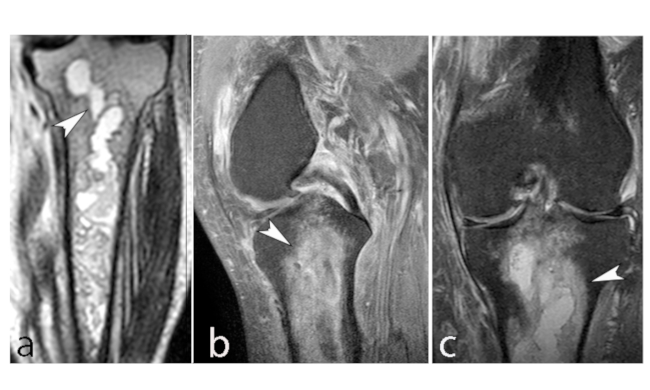

En RM en secuencia ponderada en T1, la intensidad de señal de la grasa de la médula ósea del cóndilo femoral afectado es reemplazada por un área con baja señal, asociada a una periferia de aún más baja señal (►Figs. 4 y 5).8 En la secuencia ponderada en T2 se visualiza lesión central hipointensa con área de señal alta periférica en relación al patrón de edema de la médula ósea (►Fig. 6).11

Los primeros estadios de la lesión se caracterizan por una fractura subcondral sin asociación de hallazgos osteonecróticos, reconocida en RM por una imagen lineal de baja señal ponderada en T1, subcortical, y edema periférico extenso mejor evidenciado en secuencias ponderadas en T2. Al avanzar su estadio, estas lesiones osteonecróticas muestran cambios distales por una cicatrización deficiente, lo que genera reacción y formación de cartílago con tejido fibroso indicativo de retraso o falta de unión.11